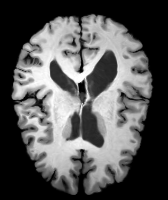

Results: All trained networks are evaluated using Dice overlap scores between predictions and the manual segmentations for the segmentation network, or between the warped moving segmentations and the target segmentations for the registration network. Tabs. 1 and 2 show results for the knee and brain MRI experiments respectively in Dice scores (%). Fig. 2 shows examples of knee MRI registrations and brain MRI segmentations.

Qualitative results: DA achieves more anatomically consistent registrations than the mono-networks on the knee (Fig. 2) and Brain MRI samples (see supplementary material).

Moving

Target

Mono-0

Mono-21

DA-1

DA-21

Mono-65

Image

Manual Seg

DA-1

Mono-5

DA-5

Mono-200